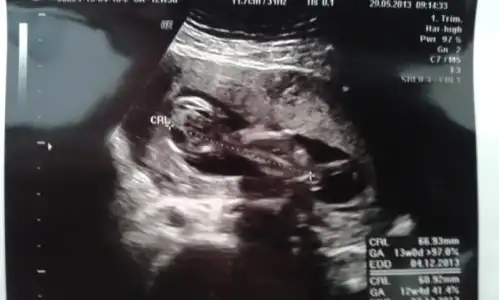

odada yalniz kalinca fotoladim hemen bebisimi. bi tanesi ilk kiprasmadan once

ki hali. bi tanesi de iki bacagi ve totosu. dr. bu resmi gorunce tahmin yapti cinsiyeti. $bebissss.webp $bacaklarr.webp :nazar:

odada yalniz kalinca fotoladim hemen bebisimi. bi tanesi ilk kiprasmadan onceki hali. bi tanesi de iki bacagi ve totosu. dr. bu resmi gorunce tahmin yapti cinsiyeti.Eki Görüntüle 723709 Eki Görüntüle 723710 :nazar:

ki hali. bi tanesi de iki bacagi ve totosu. dr. bu resmi gorunce tahmin yapti cinsiyeti.Eki Görüntüle 723709 Eki Görüntüle 723710 :nazar: